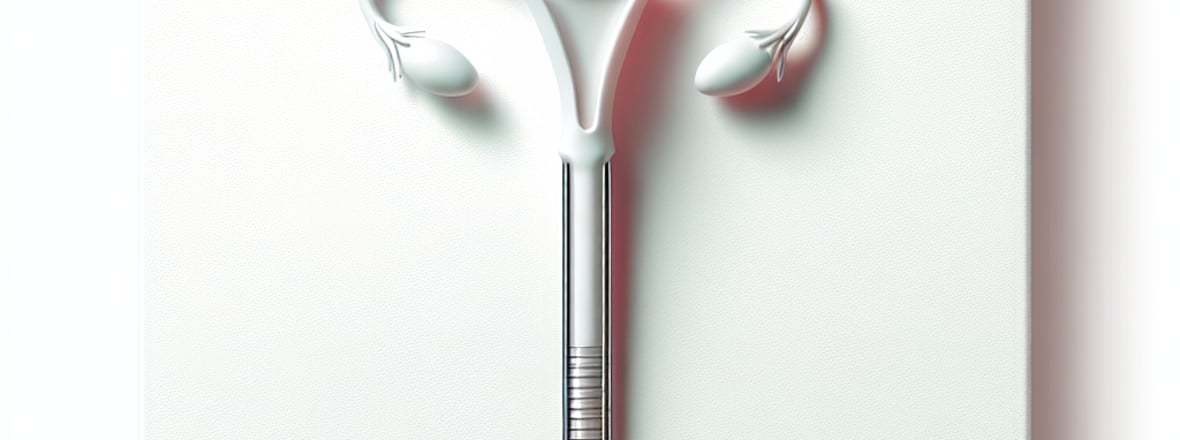

مجسات الرحم

Overview of مجسات الرحم